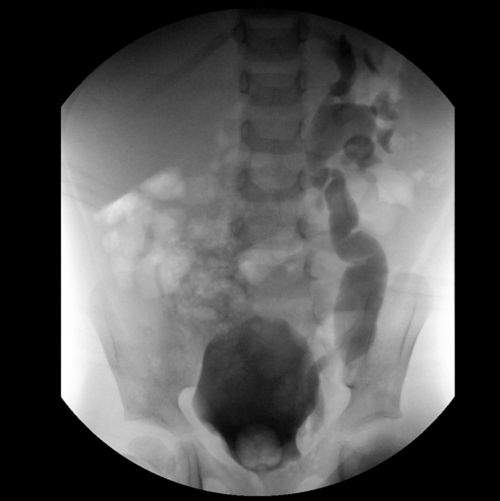

X-ray image shows beginning of VCUG test in a pediatric cancer patient.

X-ray shows progression of VCUG test in a pediatric cancer patient.

X-ray shows additional progression of VCUG test in a pediatric cancer patient.

X-ray shows last in series of VCUG test in a pediatric cancer patient.